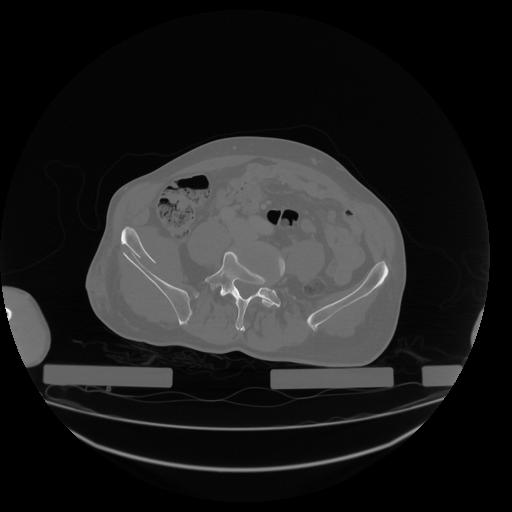

34 CUERPO,CE,Vol,1.0,CUERPO,,